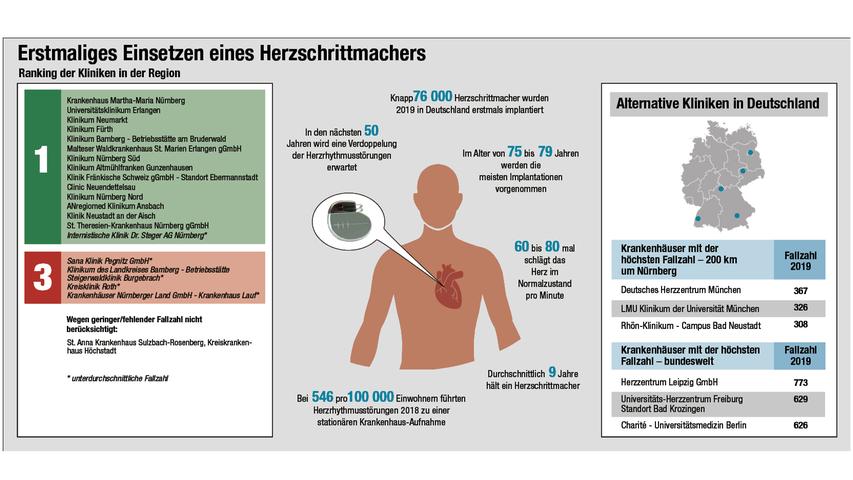

Herzrhythmusstörungen sind mit steigendem Lebensalter eine Volkskrankheit. Manchen Betroffenen ist mit einem Rhythmus-Implantat geholfen: einem Herzschrittmacher oder auch, seltener, mit einem implantierbaren Defibrillator. Bei stationär durchgeführten Herzschrittmacher-OPs erzielen viele Kardiologie-Abteilungen der nordbayerischen Krankenhäuser sehr gute Ergebnisse. Das Nürnberger Krankenhaus Martha-Maria führt in unserem Datenprojekt NN/NZ-Klinikcheck die Liste von 19 Häusern an, gefolgt vom Universitätsklinikum Erlangen und dem Klinikum Neumarkt.

Um die Grafik in voller Auflösung zu sehen, klicken Sie bitte hier.

Um die Grafik in voller Auflösung zu sehen, klicken Sie bitte hier.